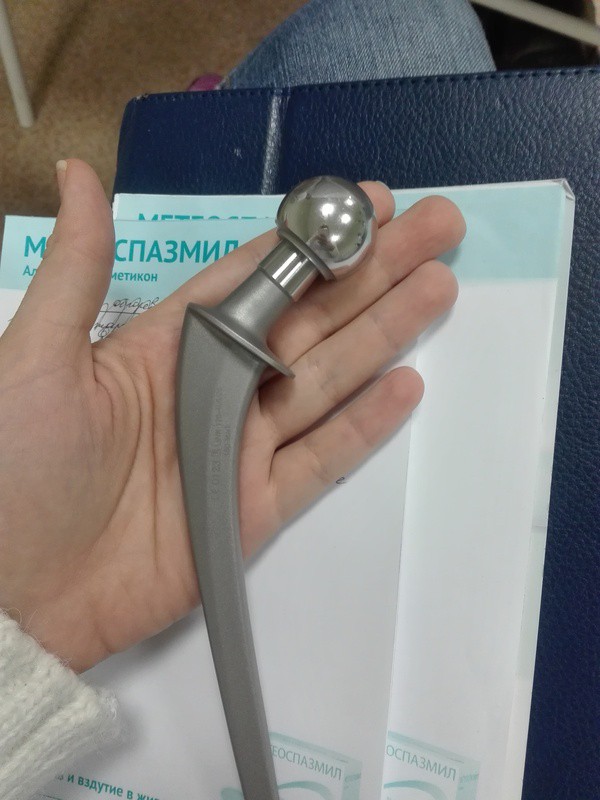

Эндопротезирование тазобедренного сустава: фото и схемы